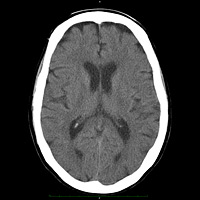

Tomografia computadorizada multi-slice (TC-MS2)

A tomografia computadorizada multi-slice (TC-MS) é um dos métodos de diagnóstico por imagem mais seguros e confiáveis actualmente. É simples, rápida e indolor. O aparelho gira os emissores de raio-x em volta do paciente fazendo radiografias transversais- do corpo, que são convertidas pelo computador, gerando as imagens digitais chamadas de 'cortes tomográficos'. A TC-MS constrói a estrutura do corpo e os órgãos internos a partir destes cortes tomográficos, possibilitando a visualização com grande precisão e confiabilidade.

As imagens geradas pela TC-MS permitem a construção tridimensional da área em estudo, tornando possível o estudo de áreas sobrepostas.